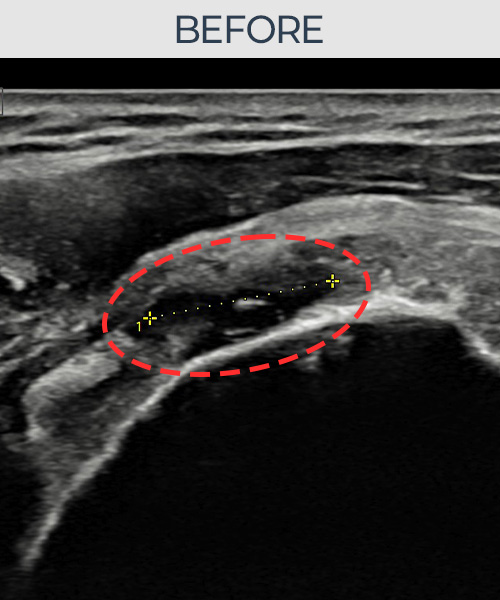

정ㅇㅇ님 · 좌측 극상근건 부착부 부분파열

좌측 어깨 부착부 부분파열로 팔을 들어 올릴 때마다 통증이 심해 내원하셨습니다. 초음파 검사에서 극상근건 부착부 에코 단절이 확인되었으며, 어깨인대 축소봉합술 후 힘줄 부착부 연속성이 완전히 회복되었습니다.